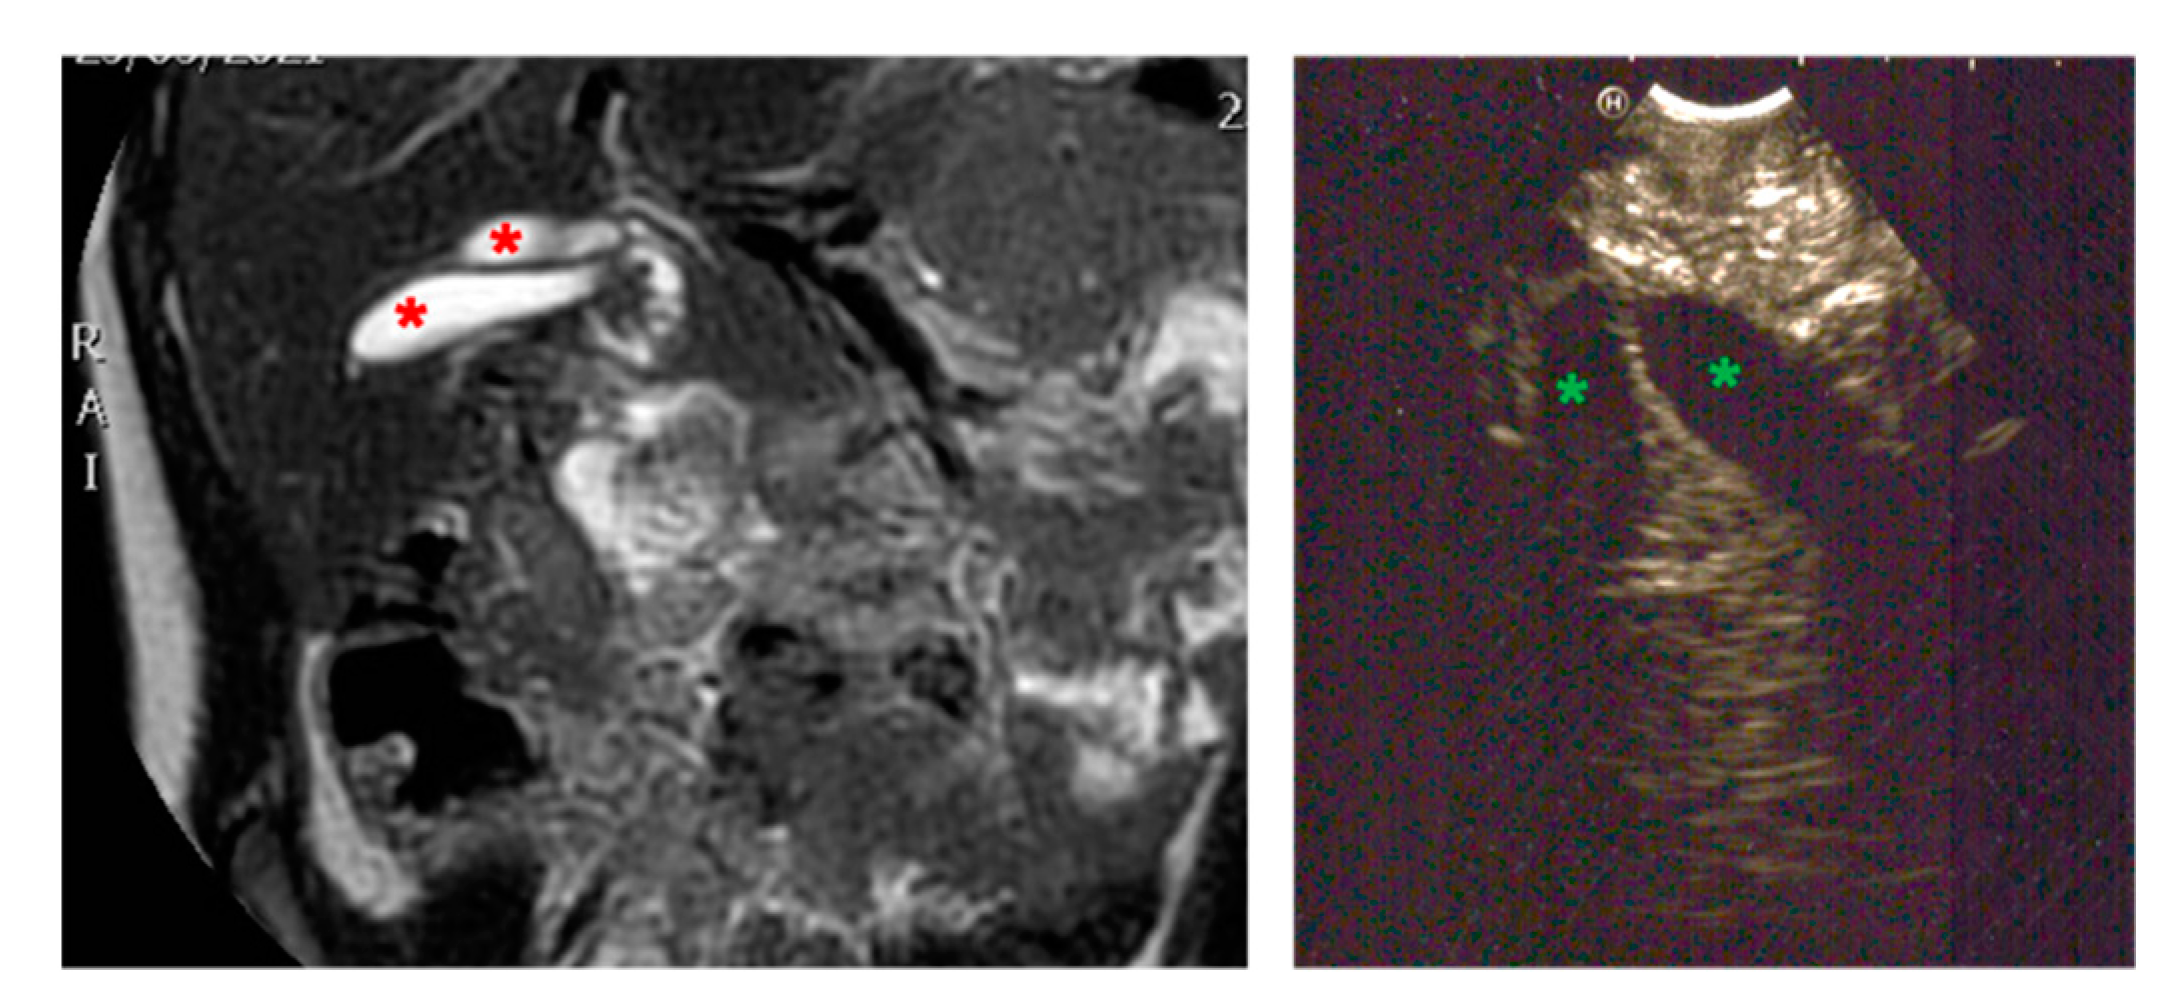

| Patients age, weight | Female 192 months 60 kg | Male 55 months 14 kg | Male 120 months 27 kg | Male 8 months 9 kg |

| Symptoms | Acute pancreatitis, pain in right hypochondrium | Icterus, pancreatitis | Chronic pancreatitis with choletithiasis, genetic-based | No |

| Diagnosis (prenatal evaluation yes/no) | Cholelithiasis and choledocholithiasis in duodenal atresia (duodeno-jejuno anastomosis at birth) and pancreas divisum (yes) | Choledochal cyst (Todani I) and choledocholitiasis (no) | Mutation of the gene PRSS1, Cholelitiasis, pancreatic duct duplication (no) | Gallbladder duplication Annular pancreas Duodenal duplication (yes) |

| Radiological investigations | US, MR, CT Scan, VR HMD | US, Cholangio MR | US, X-ray, Cholangio MR, CT, VR HMD | US, Cholangio MR, CT |

| Endoscopic instrumentation | EG-3870UTK Linear-Array Ultrasound Gastroscope | EBUS + Duodenoscope | Duodenoscope, EG-3870UTK Linear-Array Ultrasound Gastroscope | EBUS |

| Management | MIS (laparoscopic cholecisectomy) with LCBDE | 1. ERCP + sphincterotomy + stone removal 2. Open surgery: choledochal cyst removal and Roux-en-Y bilio-digestive anastomosis | 1. EUS + ERCP + stent placement + sphincterotomy + DASE; MIS (laparoscopic cholecystectomy) with LCBDE 2. ERCP and pancreatic stent replacement | MIS (laparoscopic cholecystectomies) with attempted LCBDE (failure for fibrosis) |

| Endoscopic Advantages/Limitations | Anatomical definition ERCP technically impossible for difficulties in reaching the papilla | Diagnostic and therapeutic procedures | Effective biliopancreatic drainage permitted postponed cholecystectomy and pancreatic preservation | Anatomical definition |